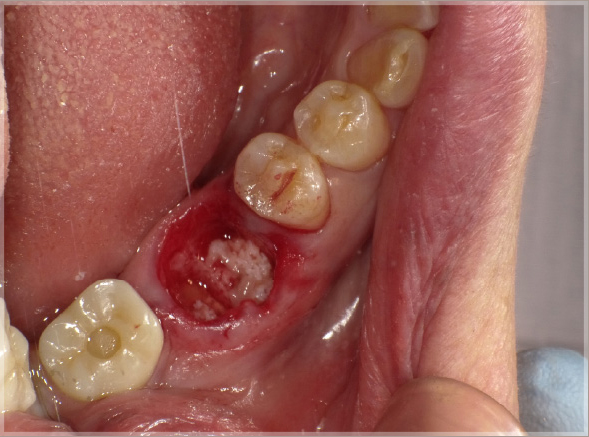

2.抜歯窩にPRGFの処置をします

③PRGF(F2+骨補填材Bio-Oss)填入

④抜歯窩を十分に満たす